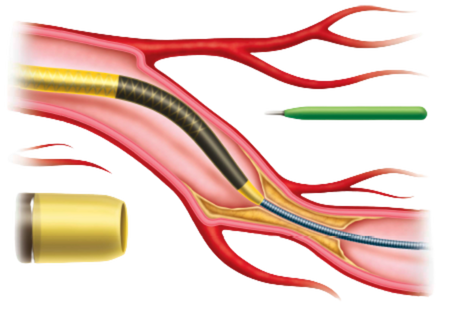

GUIDION HYDRO

DESIGNED FOR RELIABLE DELIVERY OF DEVICES TO TARGET

Guidion Hydro guide extension catheter has a radiopaque soft tip for true distal end visibility facilitating precise device positioning. The high density coiling of the distal shaft ensures optimal lumen integrity and smooth device delivery. A proximal oval push rod design keeps the profile low while securing optimal pushability.